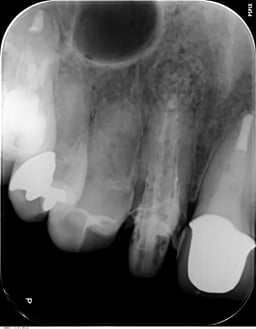

#顕微鏡下での根管治療について

支台築造(コア)の重要性